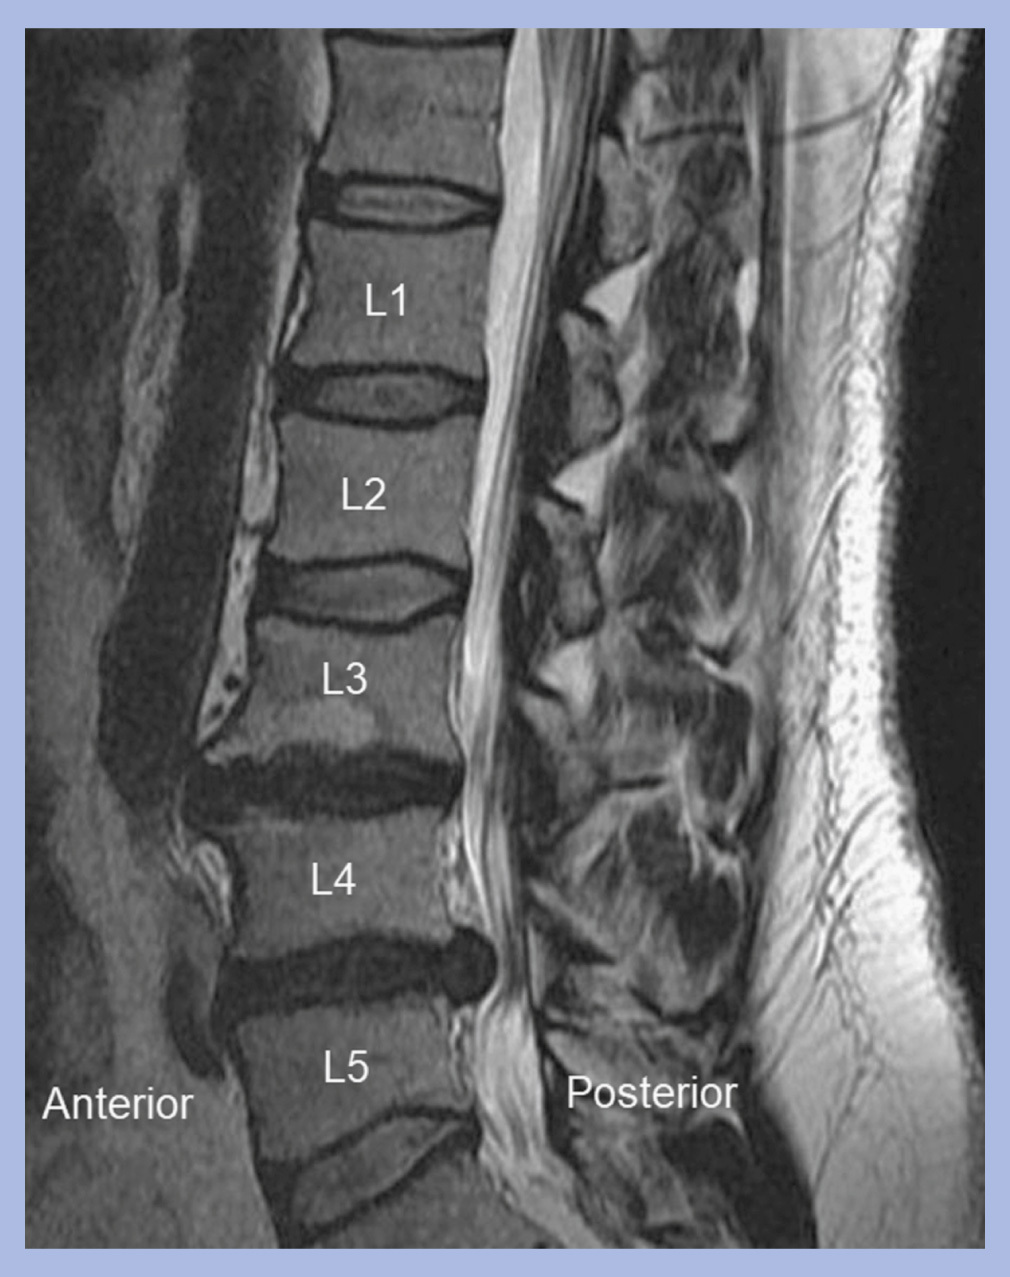

What is going on in this spine MRI?

The L4-L5 disc has herniated!